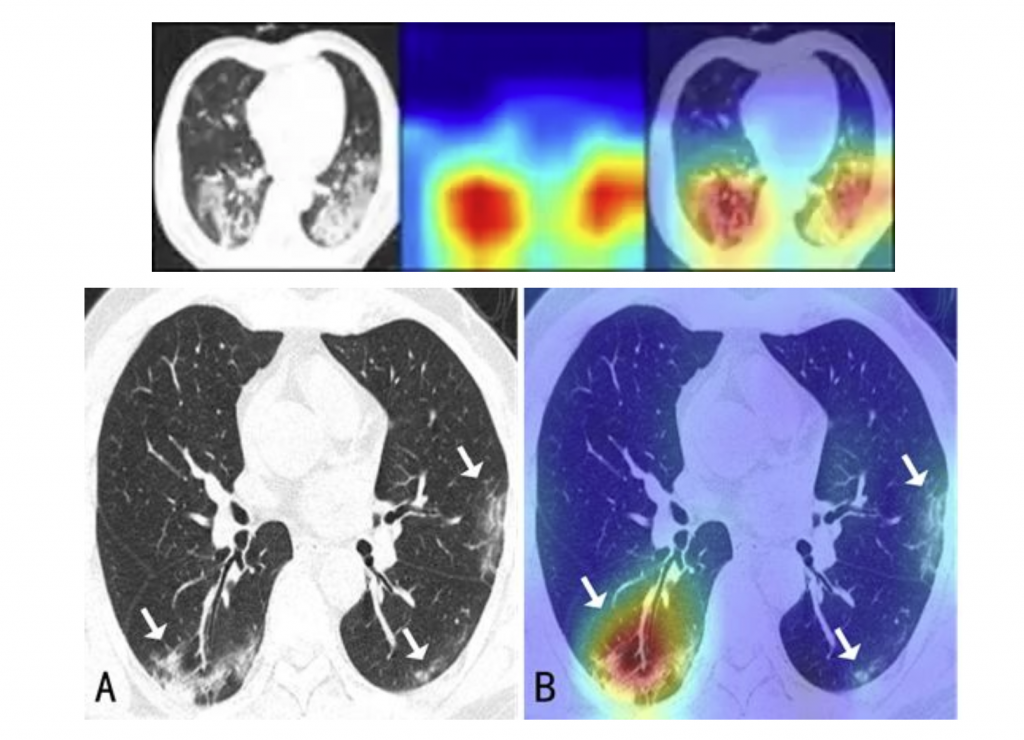

“现阶段医生需要在大量的影像数据中快速诊断出新冠肺炎的病例,此外还需要诊断出病灶分布的位置、大小等来评估严重程度。” 薛向阳介绍,针对临床的现实需求,团队将设计目标定位于 “肺炎分类鉴别” 和 “关键病灶检测” 两大功能,前者是为区别健康状态、新冠肺炎、其他病毒性肺炎、细菌性肺炎,后者则为找到并分隔出磨玻璃影等病灶区域。

而由于 CT 影像切片中的病灶区域有大有小,且往往大中小病灶区域面积悬殊,如何使算法能同时检测大、中、小各个目标是另一大难题。团队利用神经网络的层次性特点与病灶区域的大小进行对应,“网络的底层关注细节,即小病灶区域,而网络中层到高层所关注的病灶区域则越来越大,因此模型通过不同层次的加权和融合,最终便能达到同时检测大小病灶区域的目标。” 薛向阳解释道。